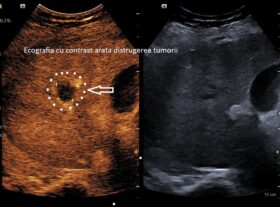

Spitalul Clinic Judeţean de Urgenţă (SCJU) Craiova a anunțat, aseară, o premieră în unitatea medicală. Este vorba despre prima ablaţie cu microunde a unei tumori hepatice. La doar o lună după intervenţie, investigaţiile imagistice au confirmat distrugerea completă a tumorii, conform precizărilor reprezentanților SCJU.

”Premieră medicală la SCJU Craiova: prima ablaţie cu microunde a unei tumori hepatice, realizată cu succes! Un pacient cu cancer hepatic a fost tratat printr-o procedură minim invazivă, fără operaţie deschisă, efectuată în Laboratorul de Endoscopie Intervenţională al Spitalului Clinic Judeţean de Urgenţă Craiova”, a anunțat Spitalul Clinic Județean de Urgență Craiova. Astfel, la doar o lună după intervenție, investigațiile imagistice au confirmat distrugerea completă a tumorii. Procedura a fost realizată de prof. univ. dr. Larisa Săndulescu, şefa Clinicii Medicale II, alături de o echipă complexă, formată din dr. Cezar Bețianu – radiolog intervenționist, dr. Andreea Stănculescu – medic anestezist, medicii rezidenți: dr. Cristiana Urhuț și dr. Aida Dănilă, asistenții medicali: Ionuț Troponete, Dana Necheș, Mihaela Călița, echipa tehnică Medtronic: Florin Stanca și Oana Arghiniei. ”Această reușită confirmă direcția modernă pe care Spitalul Clinic Județean de Urgență Craiova o urmează: medicină de înaltă performanță, minim invazivă și centrată pe pacient”, au mai menționat reprezentanții Spitalului Clinic Județean de Urgență Craiova.